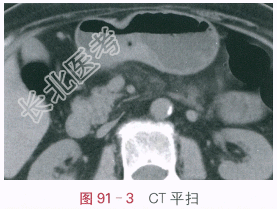

- [材料题] 王某,上腹不适、进食后饱胀1月。体格检查:左上腹轻度压痛。影像学资料:如图91-1~图91-4所示。

读片分析:(1)GI双对比相显示胃窦小弯侧较大不规则钡龛,边缘见黏膜中断、破坏,立位充盈加压相显示龛影位于腔内,边缘见环堤及指压迹征,局部胃壁稍平直、形态较固定。(2)增强CT扫描显示胃窦小弯侧胃壁局限性明显增厚,黏膜表面较大不规则溃疡形成,增强后局部胃壁明显异常强化,局部胃壁黏膜下层低密度水肿带中断。综合分析,患者考虑为胃窦小弯侧溃疡型胃癌。